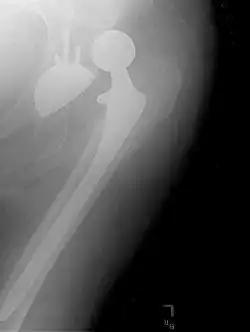

Hemiarthroplasty

Hemiarthroplasty is a surgical procedure that replaces one half of the joint with an artificial surface and leaves the other part unchanged. This class of procedure is most commonly performed on the hip after an intracapsular fracture of the femur neck (hip fracture). The procedure is performed by removing the head of the femur and replacing it with a metal or composite prosthesis. The most commonly used prosthesis designs are the Austin Moore and Thompson prostheses. A composite of metal and high-density polyethylene that forms two interphases (bipolar prosthesis) can be used. The monopolar prosthesis has not been shown to offer any advantage over bipolar designs. The procedure is recommended only for elderly/frail patients, due to their lower life expectancy and activity level. This is because over time the prosthesis tends to loosen or to erode the acetabulum.[101] Independently mobile older adults with hip fractures may benefit from a total hip replacement instead of hemiarthroplasty.[102]

X-ray of the hips, with a right-sided hemiarthroplasty